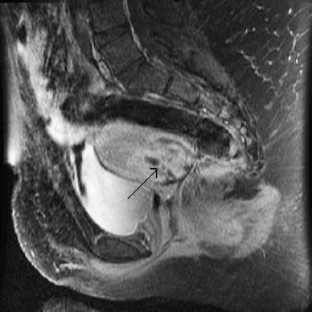

Mullerian rhabdomyosarcoma (RMS) is a rare malignancy most commonly diagnosed in childhood and adolescence. RMS of the female genital tract is often difficult to diagnose. Treatment includes chemotherapy with adjuvant surgery and/or radiation therapy reserved for persistent disease. We report a case of an 18-year-old African-American female who presented with severe menometrorrhagia, and was diagnosed with embryonal rhabdomyosarcoma of the uterus. After vincristine, dactinomycin, and cyclophosphamide failed to eradicate the central tumor, she underwent a robotic radical hysterectomy and pelvic lymphadenectomy. Mullerian rhabdomyosarcoma was once managed with multimodality therapy that often included ultraradical surgery including total pelvic exenteration. Surgical procedures that were exclusively performed via large abdominal incisions can now be completed with minimally invasive techniques. Robotic surgery can be safely and successfully applied to radical hysterectomy and lymphadenectomy for uterine rhabdomyosarcoma